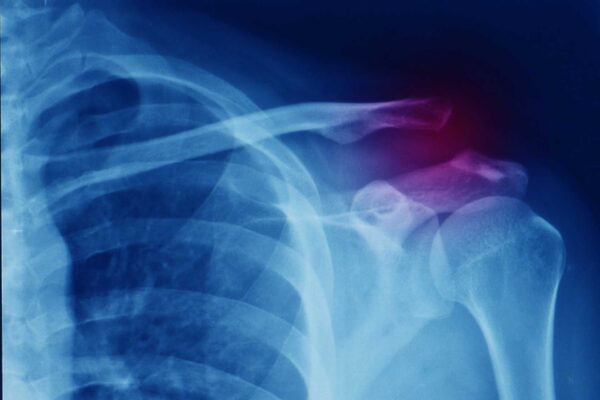

The best treatment for rotator cuff tendinopathies is a conservative approach composed of a medical component, mostly for pain relief, and a rehabilitation component to regain shoulder and full arm function.